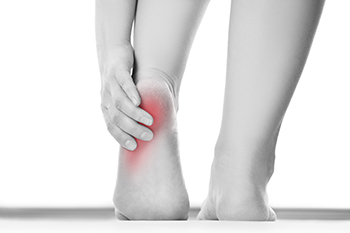

Heel pain is a frequent complaint often caused by plantar fasciitis or Achilles tendonitis. Plantar fasciitis involves inflammation of the thick band of tissue along the bottom of the foot, leading to sharp pain near the heel, especially with the first steps in the morning. Achilles tendonitis affects the tendon at the back of the heel, resulting in aching or stiffness that worsens with activity. Both conditions are commonly caused by overuse, wearing improper footwear, tight calf muscles, or sudden increases in physical activity. The heel may appear swollen, tender, or warm to the touch. Pain may range from mild discomfort to severe limitation in walking or exercise. A podiatrist can evaluate your condition through a physical examination, a review of your activity history, and imaging studies, if needed. Treatment may include stretching exercises, orthotics, anti-inflammatory medications, and changes in footwear. It is suggested that you schedule an appointment with a podiatrist if heel pain continues or worsens.

Many people suffer from bouts of heel pain. For more information, contact Edward Orman, DPM of Honeygo Podiatry. Our doctor can provide the care you need to keep you pain-free and on your feet.

Causes of Heel Pain

Heel pain is often associated with plantar fasciitis. The plantar fascia is a band of tissues that extends along the bottom of the foot. A rip or tear in this ligament can cause inflammation of the tissue.

Achilles tendonitis is another cause of heel pain. Inflammation of the Achilles tendon will cause pain from fractures and muscle tearing. Lack of flexibility is also another symptom.

Heel spurs are another cause of pain. When the tissues of the plantar fascia undergo a great deal of stress, it can lead to ligament separation from the heel bone, causing heel spurs.

Heel pain should be treated as soon as possible for immediate results. Keeping your feet in a stress-free environment will help. If you suffer from Achilles tendonitis or plantar fasciitis, applying ice will reduce the swelling. Stretching before an exercise like running will help the muscles. Using all these tips will help make heel pain a condition of the past.